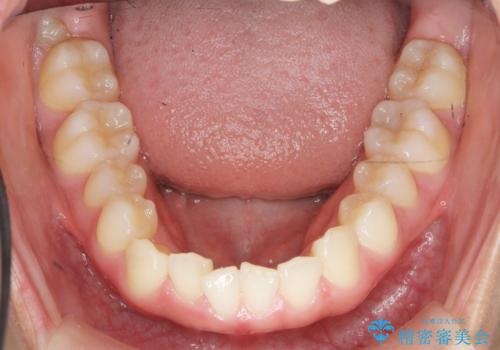

マウスピース矯正で前歯のガタつきを改善

- 上下の前歯のガタつきの改善を求めて、矯正治療を希望され来院されました。

矯正検査の結果、マウスピース矯正システム インビザラインの適応であることからワイヤーを用いず矯正治療を進めることとしました。

1日20時間以上の使用時間をきっちりと守っていただけたため、良好な治療結果、歯並びを手に入れることができました。